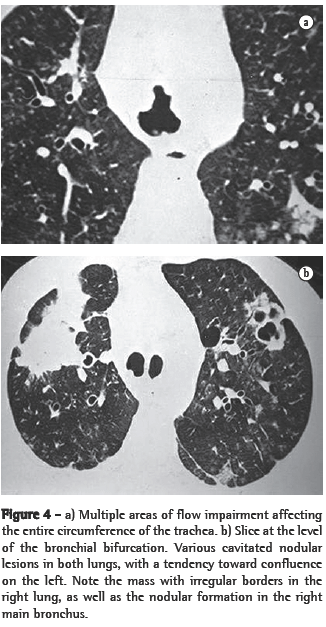

In all eight cases, the CT scans revealed polypoid formations in the trachea. In one case, injury to one of the main bronchi was identified. Seven patients presented involvement of the pulmonary parenchyma. In all eight cases, there were cavitated polypoid lesions, with irregular internal borders and walls of various thicknesses, multilobulated in six cases and presenting confluence of the lesions in five (Figures 1 through 5). Solid nodules were seen in six patients. An air-fluid level was observed in only one patient. The lesions were predominantly in the lung bases in three patients and in the middle thirds in two, whereas they were evenly distributed in two. In one patient, the lesions were accompanied by a mass, and, in another patient, they were accompanied by consolidation. In the latter case (Figure 5), there was malignant degeneration in multiple lesions. Signs of air trapping were also observed in one case. There were no identified instances of lymph node enlargement or pleural effusion.

Chest X-rays can occasionally produce findings suggestive of the disease, such as the combination of solid or cavitated pulmonary nodules and vegetative nodular lesions in the trachea or in the main bronchi. Unlike the pulmonary nodules, which are often identified on simple chest X-rays, intralumen papillomas in the trachea or bronchi are rarely visible on X-rays.(4) In practice, therefore, the disease is rarely diagnosed on the basis of chest X-ray findings. The nodules are typically multiple, well defined, of various dimensions, cavitated and thick-walled, being more numerous in the basal and posterior lung regions.(3,4) The cavitated nodules can be air-filled or, when infected, can present an air-fluid level.(4)

Chest X-rays are inferior to CT scans of the chest, especially those performed using spiral CT (volumetric acquisition), in the initial phases of pulmonary dissemination, due to the fact that CT better characterizes and allows better visualization of nodular tracheobronchial vegetation, Tomographic findings include focal or diffuse airway narrowing caused by the nodules. The nodules form on the mucosal surface, and their invasion into the lumen is best evaluated using CT.(3) These alterations are easily correlated with the disease when there is a clinical history of papillomatosis.(4) Other findings related to airway obstruction and accompanying infections are atelectasis, consolidations, air trapping and bronchiectasis.(2-4) In our sample, polypoid formations in the trachea were observed on all of the CT scans Seven patients presented involvement of the pulmonary parenchyma, characterized by cavitated polypoid lesions with irregular internal borders and walls of various thicknesses, with a multilobulated aspect and a tendency toward confluence. Solid nodules were seen in six patients. None of the patients presented lymph node enlargement or pleural effusion.